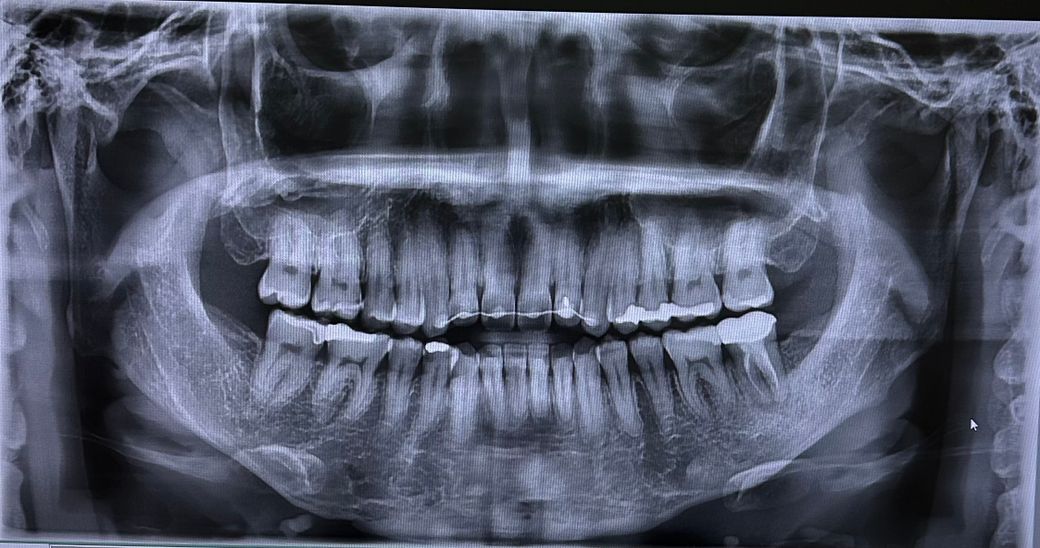

골격정 비대칭은 치아 교정만으로는 해결할 수 없고 양악수술을 통해 교정할 수 있습니다만

골격적으로나 치열로나 사진으로 보기에는 교정의 필요성이 딱히 보이지는 않습니다.

물론 해당 사진만으로 교정의 필요성을 판별하긴 어렵고 전반적인 교합 관계를 봐야 알 수 있습니다.

어떤 이유에서 재교정을 하려고 하시는지는 모르겠지만 안면비대칭의 이유로 하시는 것이라면 치아교정만으로 해결하기는 어렵습니다.

파노라마 사진 한장만으로는 단정하기 어렵지만 본인이 재교정 원하면 재교정 시도해 볼 수 있을 것으로 보입니다.